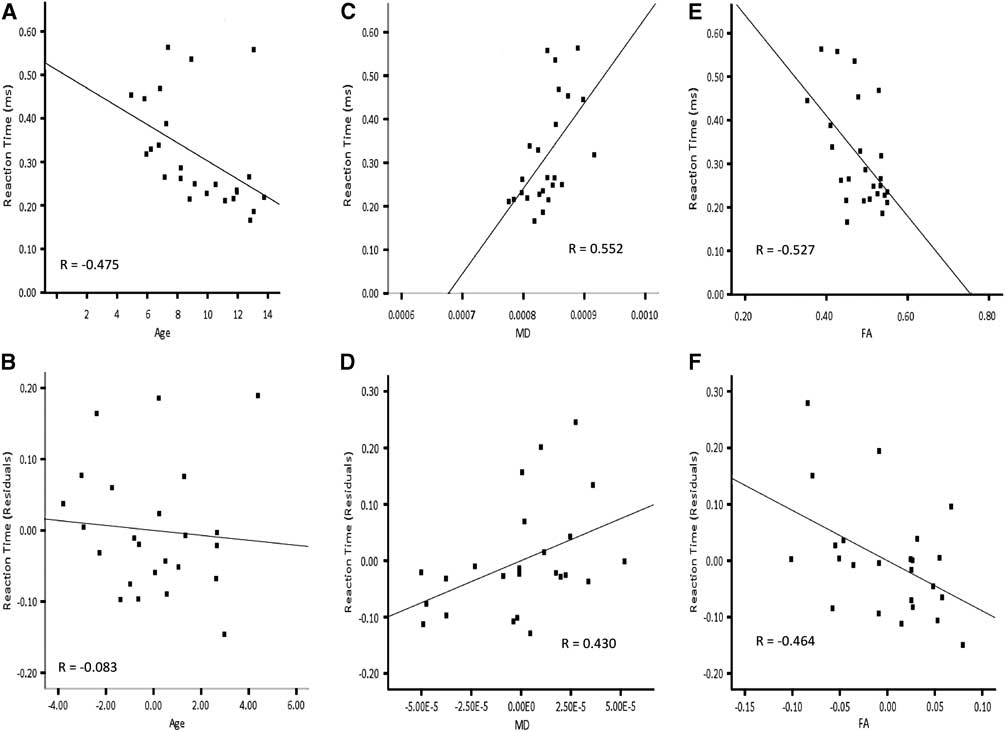

Based on higher-order regression analysis, the structure of the cortico-spinal tracts in the left hemisphere, the inferior fronto-occipital fasciculus in the right hemisphere and the optic radiations bilaterally showed age-related changes, and also predicted reaction time. Hence, these connections were included in the final model predicting right hand reaction time. The linear term for age was included in the hierarchical model. The linear terms for FA of the cortico-spinal tract of the left hemisphere, MD of the inferior fronto-occipital fasciculus of the right hemisphere, MD of the optic radiations in the right hemisphere and the quadratic term for MD of the optic radiations in the left hemisphere were included together in a stepwise manner. AD of the optic radiation in the right hemisphere was not carried forward to the primary analyses to avoid collinearity with MD. Age accounted for a significant amount of the variance observed for reaction time of the right hand when entered into the regression model first (Table 4a; Model 1:1). Adding FA of the cortico-spinal tract in the left hemisphere and MD of the inferior fronto-occipital fasciculus of the right hemisphere to the model in a stepwise manner significantly increased the amount of predicted variance in reaction time by approximately 26%. Conversely, there was no significant increment in predicted variance when age was entered into the model after FA of the cortico-spinal tract in the left hemisphere and MD of the inferior fronto-occipital fasciculus of the right hemisphere (Table 4a; Model 1:2). The striking relation between age and reaction time of the right hand was no longer apparent after accounting for FA of the cortico-spinal tract in the left hemisphere and MD of the inferior fronto-occipital fasciculus in the right hemisphere (Figure 5). On the other hand, the relation between reaction time of the right hand and FA of the cortico-spinal tract in the left hemisphere remained evident after accounting for age and MD of the inferior fronto-occipital fasciculus in the right hemisphere. Moreover, the correlation between reaction time of the right hand and MD of the inferior fronto-occipital fasciculus in the right hemisphere was still apparent after accounting for age and FA of the cortico-spinal tract in the left hemisphere. DTI indices from the optic radiations did not contribute unique variance and were not maintained in either model.

Fig. 5 Correlations for right hand reaction time and residuals as a function of age, MD of the right inferior fronto-occipital fasciculus and FA of the left cortico-spinal tract. Note that the correlation between age and reaction time (A) is not apparent in after accounting for MD of the right inferior fronto-occipital fasciculus and FA of the left cortico-spinal tract (B). The correlation between MD of the right inferior fronto-occipital fasciculus and reaction time (C) remains after accounting for age and FA of the left cortico-spinal tract (D). The correlation between FA of the left cortico-spinal tract and reaction time (E) is still evident after accounting for age and MD of the right inferior fronto-occipital fasciculus (F).

Because of the curvilinear relation between age and reaction time of the left hand, the quadratic term for age was included in the final model predicting left hand reaction time. Furthermore, MD of the optic radiations and CST in the right hemisphere were included in a stepwise manner, considering the age-related changes in these tracts and that they predicted left hand reaction time. RD of the optic radiation in the right hemisphere was not included in the primary analyses to avoid collinearity with MD. Neither age nor MD of the optic radiation accounted for unique variance of left hand reaction time when the other was included in the model (Table 4b; Model 2). The fact that age and MD together account for so much variability in reaction time, but so little unique variability, suggests that the impact of these two variables on reaction time is difficult to separate statistically. MD of the right CST did not contribute unique variance and was not maintained in either model.